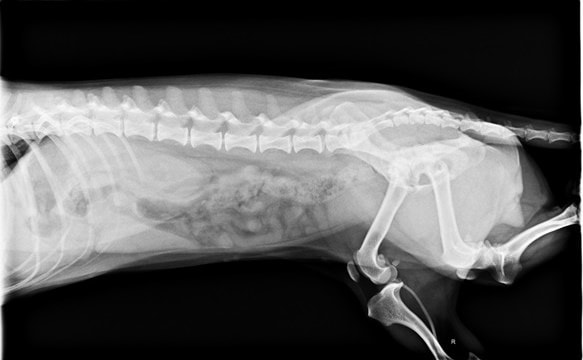

3.X光片

左邊膝蓋是鬆的,但走路看起來很好

沒有跑一跑突然掰咖,舉例來說紅貴賓容跑一跑跛腳,膝蓋會甩一下

膝關節異位這類的情況,但如果不影響日常生活就不需要手術的

左腳的膝關節有點偏移

tila是臘腸犬,可以補充關節軟骨保護劑,當作保養

有稍微擠迫一點點,但基本神經學檢查反應~腳腳的肌肉都非常好

髖關節的部分和以前沒差多少,以100分來說算85分

以臘腸品種這年紀來說算漂亮的,即早保養最好、神經傳導目前看也都好

髖關節右腳比左腳漂亮一點點 ((很愛用漂亮形容

骨骨頭左邊沒有那麼圓潤、股骨頸沒有過度的增粗

胸腰椎,每個椎體間隔都還漂亮、不會過度狹窄

胸腔、腹腔、心肺都很乾淨!漂亮!

血管很明顯

胸腔也都乾淨、無擴張,心臟大小跟以前差不多

心臟看起來很大,但臘腸狗的比例算是標準的

不用進階心臟照超音波